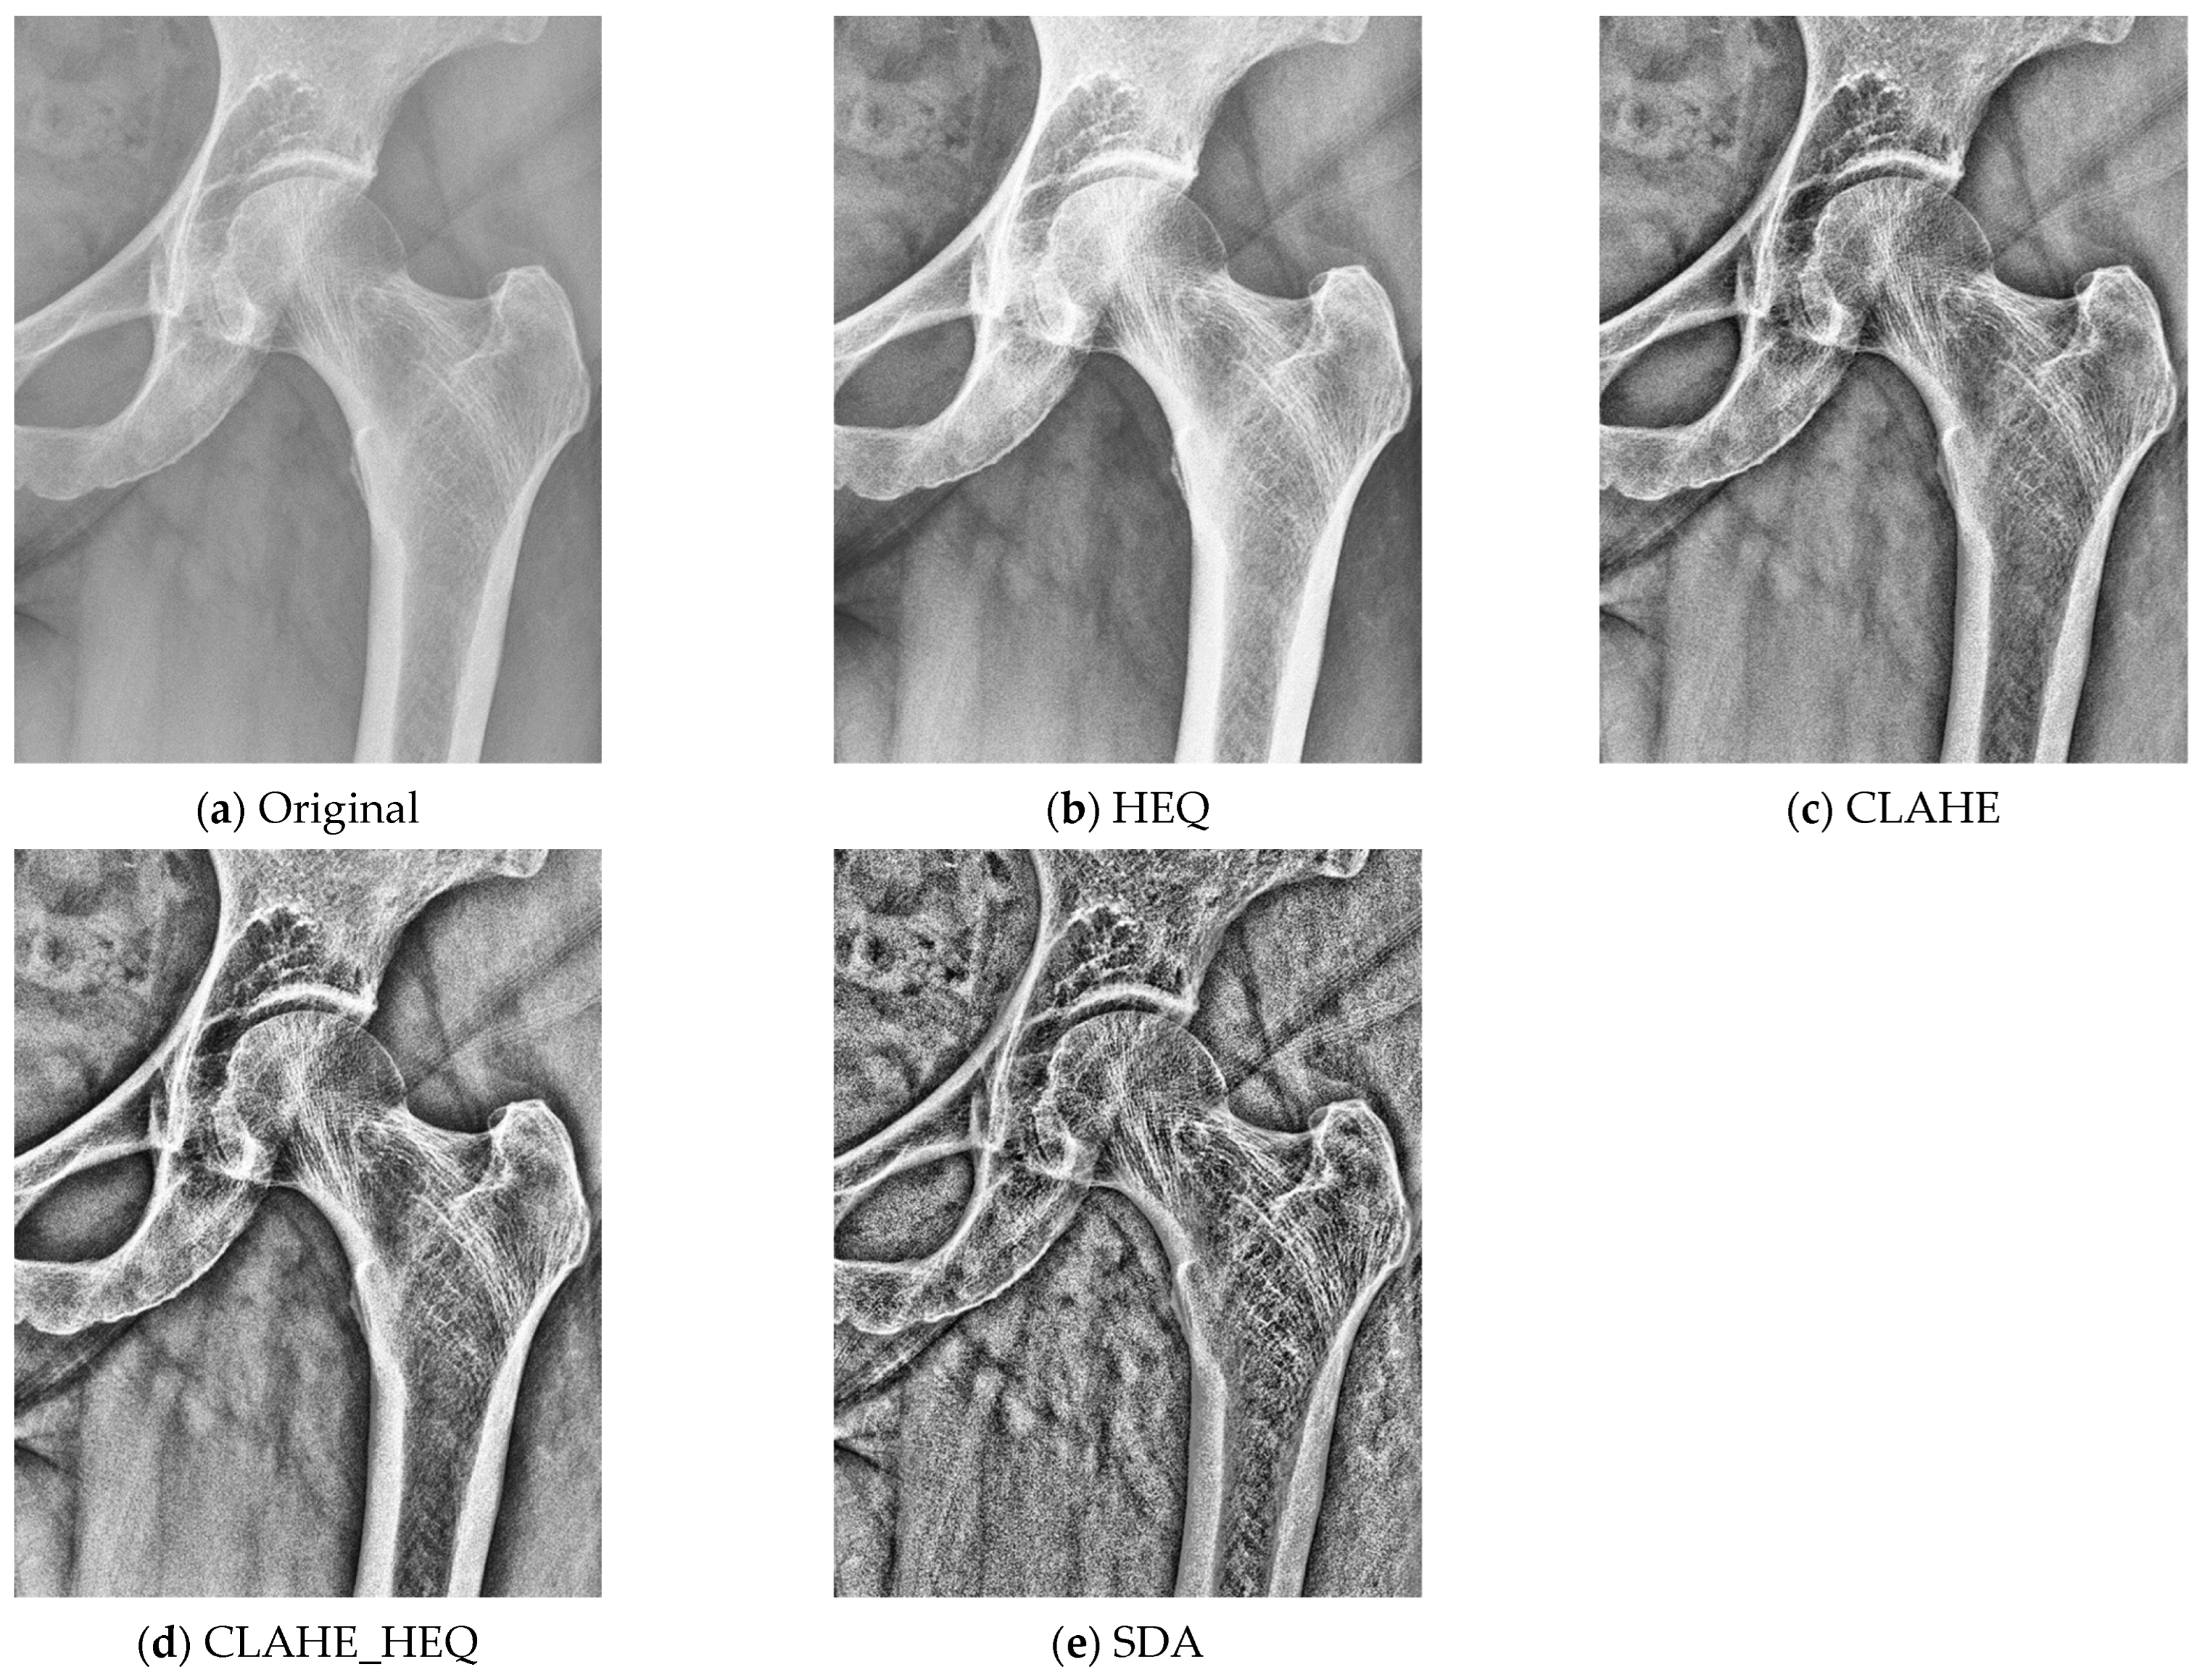

2.3. Preprocessing